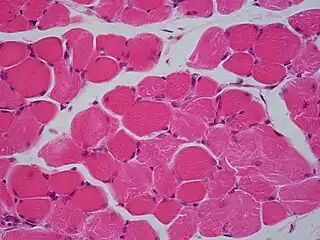

- Músculo esquelético

El músculo esquelético es considerado un verdadero sincitio anatómico, pues cada célula presenta múltiples núcleos, originada por la fusión de múltiples células. Los mioblastos comienzan a multiplicarse, influidos por factores de crecimiento como el FGF. Los receptores integrinas de las fibronectinas y otras moléculas como las cadherinas los obligan a reconocerse, alinearse y adherirse, para posteriormente fusionarse en células musculares sincitiales. Este último proceso está mediado por meltrinas —unas metaloproteasas—.[10] En cultivo, los mioblastos forman el sincitio al proliferar y fusionarse mientras producen proteínas contráctiles. Este proceso es cooperativo, de tal forma que la fusión celular altera el medio de cultivo para inducir la fusión de otros mioblastos.[27]

El sincitio del músculo esquelético permite una rápida contracción coordinada de los músculos en toda su longitud. El potencial de acción se propaga a lo largo de la superficie de la fibra muscular desde el punto de contacto sináptico con la neurona motora.[28] En estados patológicos como la miopatía, la presencia de sincitio permite la viabilidad muscular, porque los focos de necrosis de una parte del músculo esquelético no resultan en la necrosis de las secciones adyacentes de esa zona ya que estas regiones tienen su propio material nuclear, aunque algunos de los segmentos supervivientes queden sin inervación por la pérdida de continuidad con la unión neuromuscular.[29]